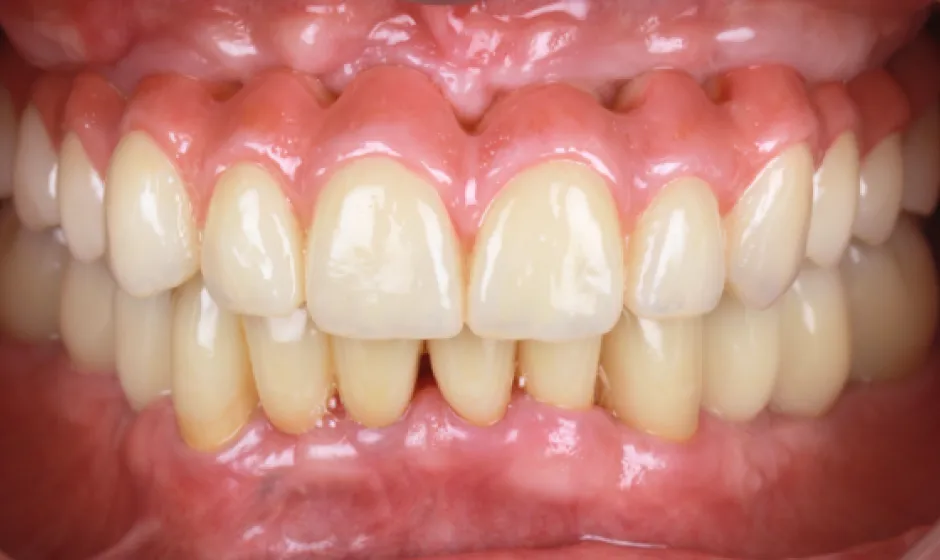

03歯がボロボロの方への

全顎治療むし歯や歯周病が広がり、「どこから治せばいいのか分からない」状態は、痛みだけでなく食事や会話、見た目のストレスにもつながります。医療法人大杉歯科医院では、まず精密に検査し、残せる歯・治療が必要な歯を見極めたうえで、治療の優先順位を整理します。仮歯で噛み合わせを整えながら、補綴やインプラントなどの選択肢を組み合わせ、機能と審美の両立を目指します。

いきなり理想を押しつけるのではなく、現実的に続けられる計画で、お口全体を立て直す治療をご提案します。症例1

- 治療名

- 重度虫歯からの全顎インプラント治療

- 患者様

- 70代男性

- 執刀医

- Dr. 大杉

- 治療期間

- 1年6ヶ月

- 治療費

- 上顎:4,620,000円(税込)

下顎:3,630,000円(税込) - リスク

- ラミックのすり減りを防ぐために、ナイトガードを作成しています。毎晩使用することで、セラミックを長持ちさせることができます。